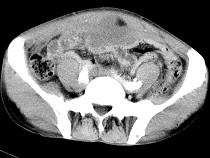

问题 男,56岁,无规律上腹痛,左锁骨上淋巴结肿大,消瘦、乏力,影像检查如图,最可能的诊断是()

选项 A.腹膜结核 B.胃溃疡穿孔 C.胃癌并盆腔种植 D.胃及腹腔淋巴瘤 E.肠系膜淋巴管瘤

答案 C